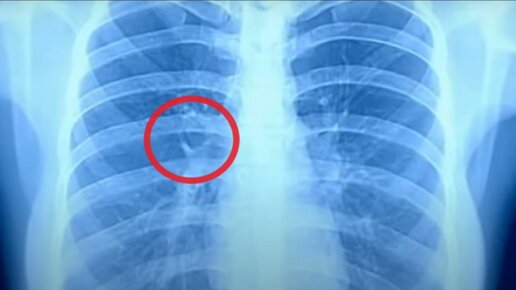

Что показывает рентген лёгких при коронавирусе и как выглядят лёгкие при ковиде?

Коронавирусная инфекция становится причиной поражения легочной ткани, поэтому большинство пациентов проходят рентгенологическое обследование.